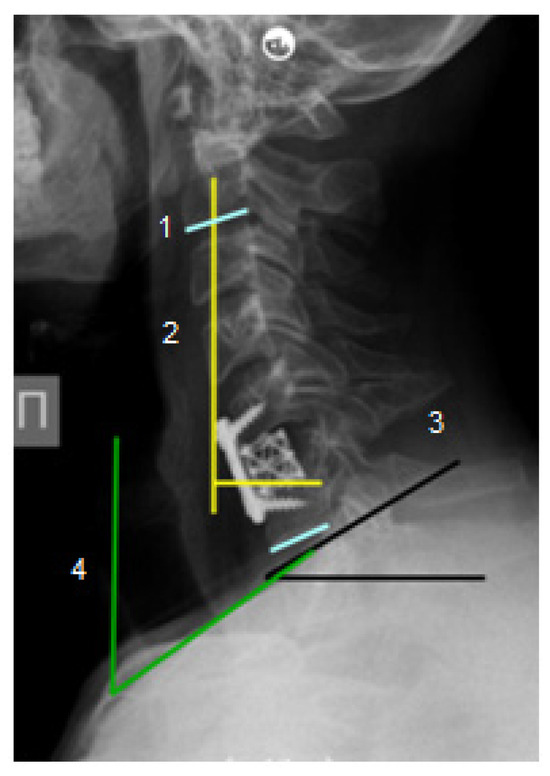

Figure 2.

Pre- and postoperative radiological findings of a patient with C1-2 spondylitis.